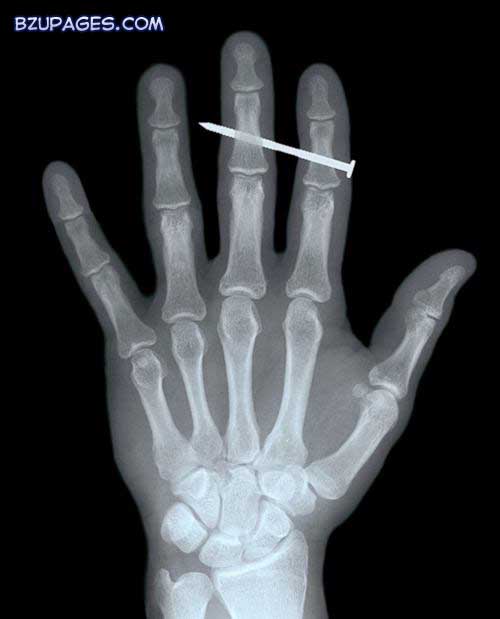

The comical yet disturbing results are taken from hospitals around the world and show how accidents come in all shapes and sizes. This X-ray shows a nail (upper centre) lodged in bones of the index and middle fingers of an adult male, having penetrated through the skin